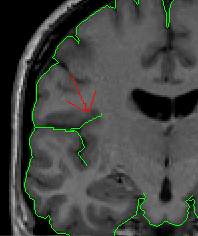

Because proper segmentation of the cerebral exterior includes a clearly drawn in Sylvian Fissure, segmentation of the insula in the more posterior coronal slices is simply a matter of “extending” these drawn in lines to the medial white matter (Fig 4-5)

Figure 4                  Figure

5